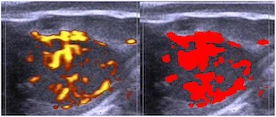

Comparación entre la palpación transrectal, el modo B y la ecografía Doppler para evaluar la función lútea en bovinos Holstein

Introducción: A lo largo de los años, los métodos más comunes para monitorear la salud reproductiva en el ganado han variado, desde la palpación transrectal hasta la ecografía en modo B. Hoy en día, algunos equipos de ultrasonido portátiles incluyen el modo Doppler. Por lo tanto, el objetivo de este estudio fue comparar la precisión de los diferentes métodos para evaluar la funcionalidad del cuerpo lúteo (LC). >>>